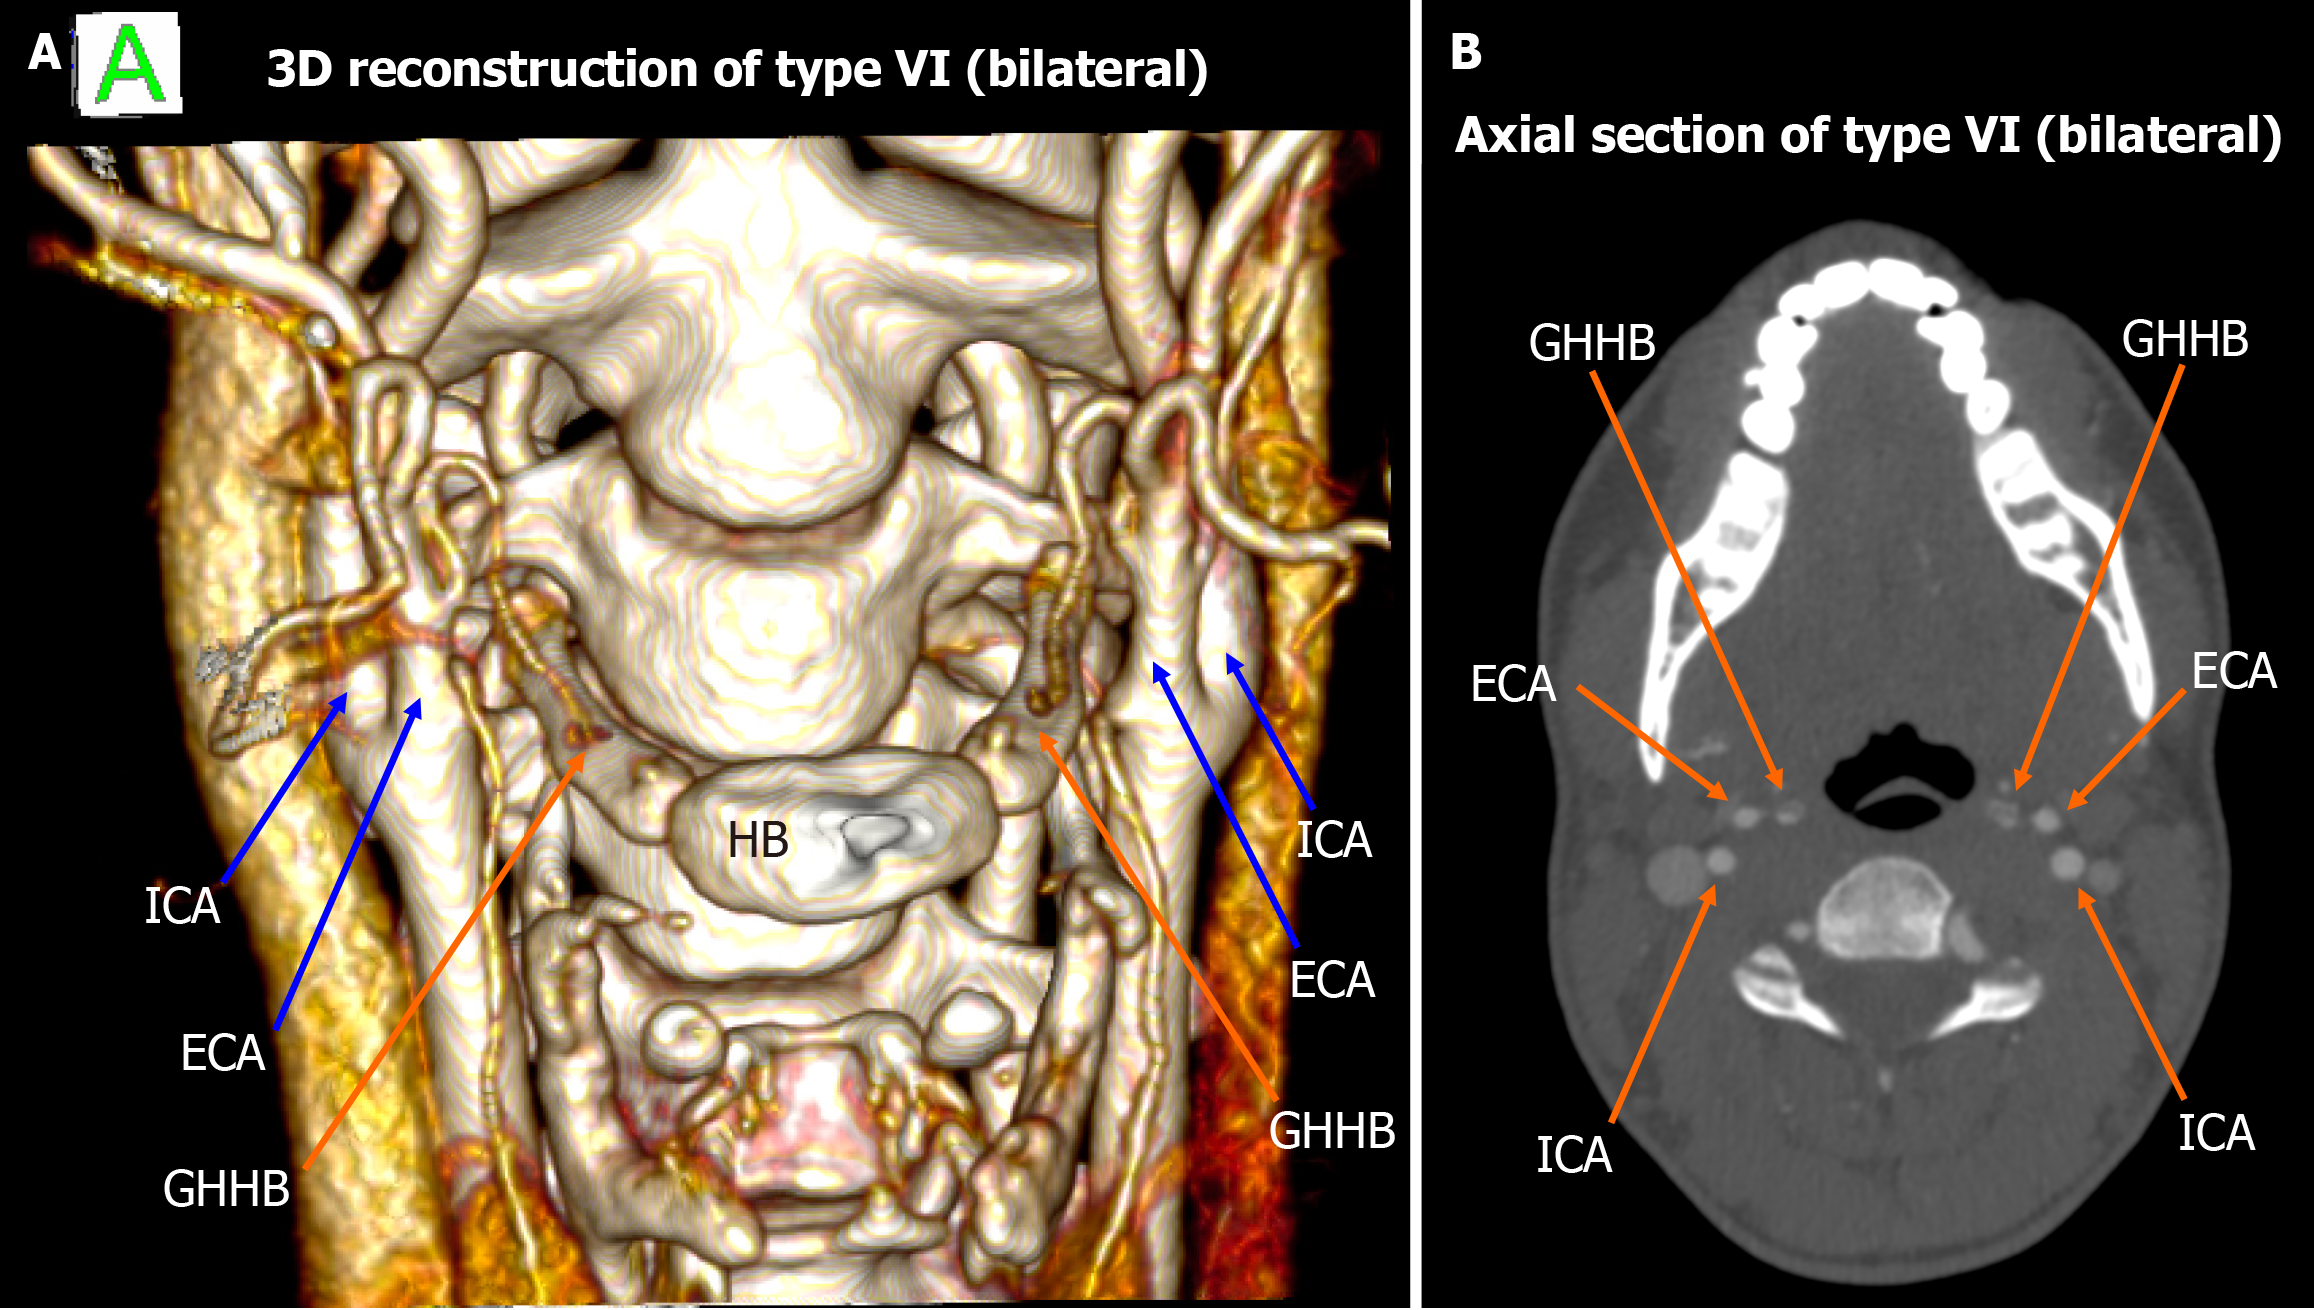

Figure 3 Type VI bilateral configuration.

A: 3D reconstruction shows the external carotid arteries bilaterally lateral to the greater horn of hyoid bone; B: The axial view demonstrates the symmetry of this type VI pattern. ICA: Internal carotid artery; ECA: External carotid artery; GHHB: Greater horn of hyoid bone; HB: Hyoid bone.